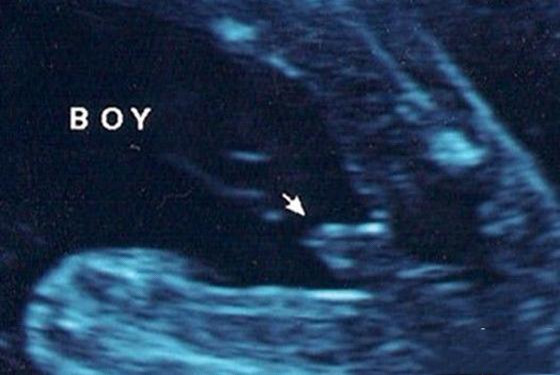

1、男宝宝的B超图:男宝宝的B超图上其实是能看到小鸡鸡的,图片的红圈处就是。这张图片上的小鸡鸡非常清晰,医生很厉害,她取的那个角度就是宝宝的屁股正下方,看的特清楚。

"凸出的东西" 是他的标记: 你们看到圆圆的是DANDAN,如果看到圆圆的加小肠的就是全部JJ